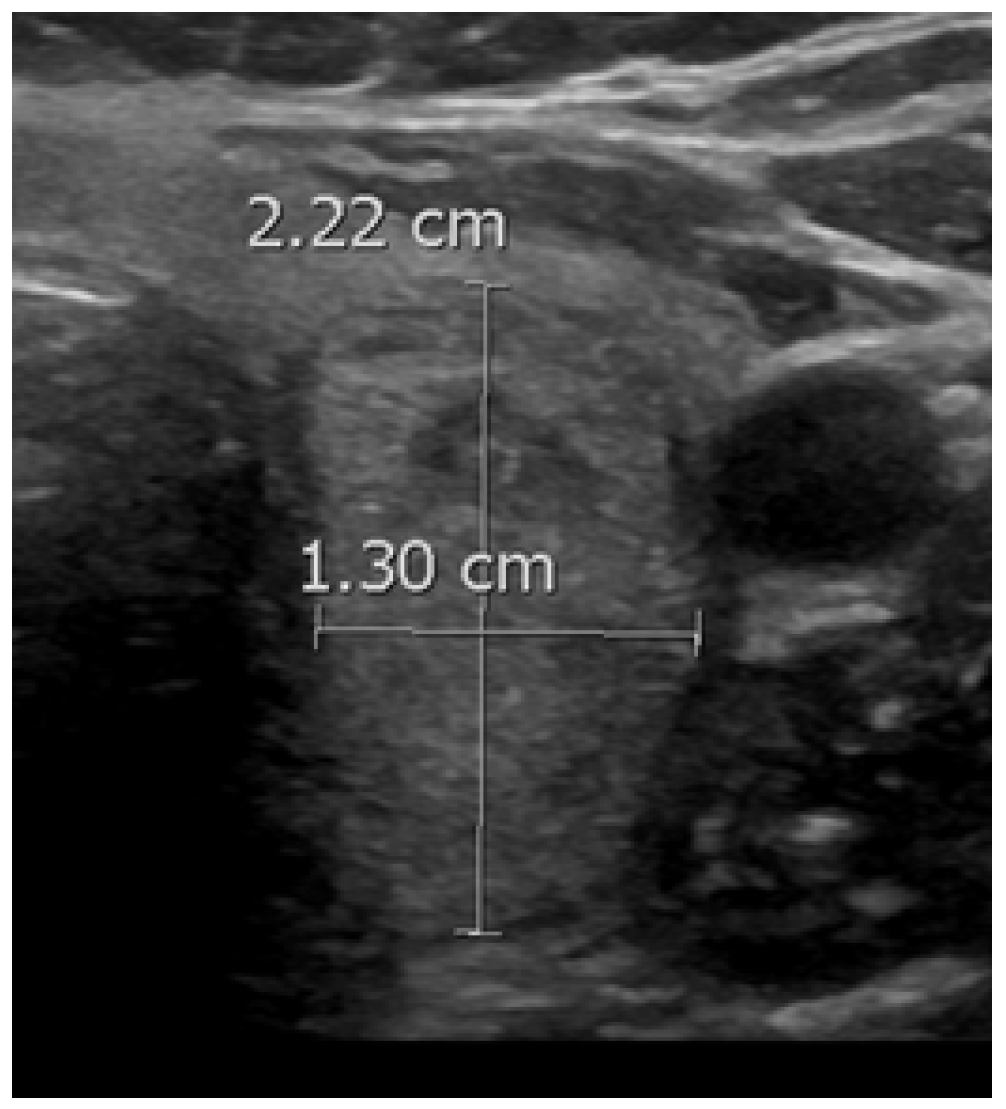

PEF refers to distinct echogenic dots ≤1 mm within a thyroid nodule (Figure 2) [24]. Unlike macrocalcifications, PEF do not cast a posterior acoustic shadow, although they can be associated with small comet tail artifacts. It is important to differentiate PEF from echogenic foci > 1 mm, which can be associated with more pronounced V-shaped comet tail artifacts; the latter are characteristic findings in benign colloid nodules [24]. The underlying etiology in PEF is unclear; in some instances, these may represent psammoma bodies in papillary cancers, while in others, they may indicate the back wall of microcysts [24]. PEF were observed in 64.7% of the malignant nodules compared to only 9% of the benign nodules in our study. Multivariate regression revealed that PEF were associated with a significant cancer risk, yielding an OR of 11 (95% CI, 6.4 to 18.8), at p < 0.001. Our findings agree with the literature. Nabahati et al. conducted a study involving 1129 nodules and found a significant correlation between PEF and malignancy, with ORs of 3.7 (95% CI, 2.3 to 5.8) in a univariate analysis and 1.9 (95% CI, 1.1 to 3.2) in a multivariate analysis [48]. Sohn et al. examined 1018 nodules and found a significant correlation between intra-solid PEF without comet tail artifacts and cancer risk, yielding an OR = 8.1 (95% CI, 3.6 to 17.9), at p < 0.001 [49]. Lastly, Ha et al. studied 1112 nodules and reported that PEF with comet tail artifacts were associated with a malignancy rate of 77.8% in solid and predominantly solid nodules [50].

Figure 2. A malignant nodule (arrow) with punctate echogenic foci.